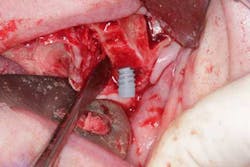

Surgery commenced. Implants on the lower arch were placed first (figures 7 and 8) and then we switched to the maxillary. The teeth were removed (figures 9 and 10) and the ridge was evened out (figures 11-13). The implants were aligned with the denture (figure 14) and then placed accordingly (figures 15-17). Healing caps were put on, and we were ready to start the restorative phase (figures 18-19).